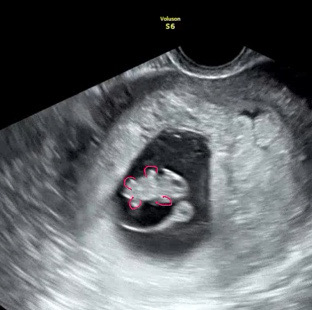

8주2일차 젤리곰이예용:)

먹덧이 와서 꿀꿀이가 되고 있는 와중에 오늘 젤리곰 보고왔어여>< 심소 들을 때까진 신기하고 묘하고 그랬는데 막상 형태를 보니까 너무 귀여워요